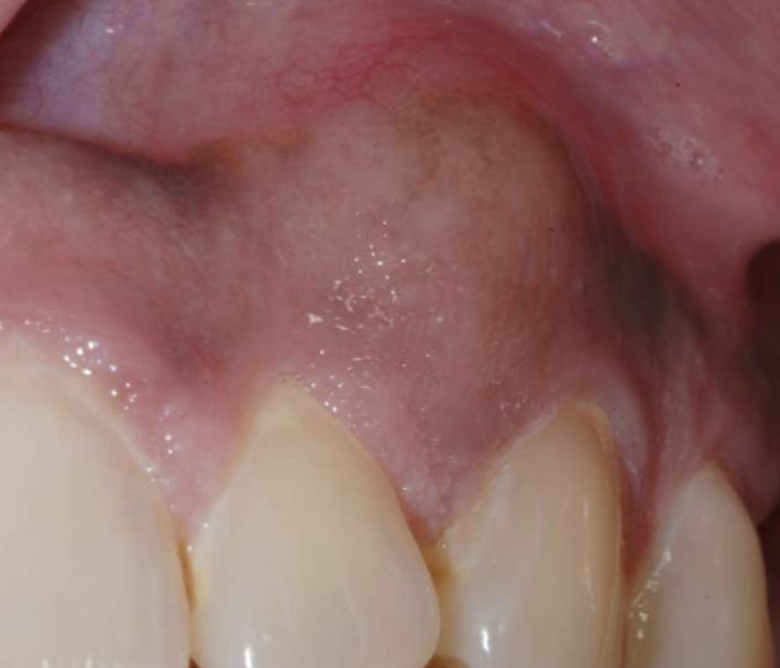

• Painless, non-ulcerated gingival nodule

• Resembles pyogenic granuloma or fibroma

• Usually < 1.5cm

• Superficial alveolar bone may be eroded

What benign tumor?

Peripheral Ameloblastoma

what is the average age of Peripheral Ameloblastoma?

52

which jaw do Peripheral Ameloblastoma have a predilection for?

manible